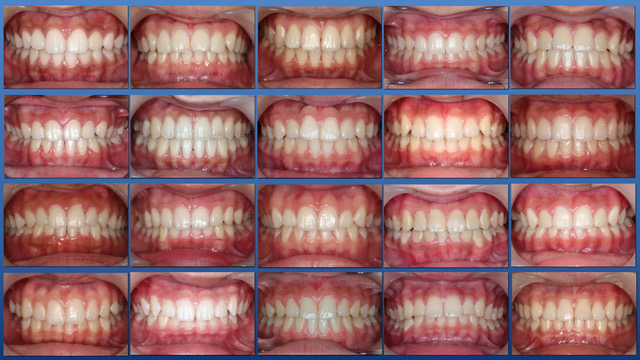

● 咬合育成

子どもたちを虫歯のないきれいな歯並びに誘導していくことが咬合育成で、歯並びが悪くなってから治療する矯正歯科治療とは異なる治療の仕方です。開業時から来院していたこどもたちをどうしたらきれいな歯並びにできるのかを研究してきました。いまではその成果が上がるようになり多くの子どもたちが健康できれいな歯並びをもつ大人になって来院するようになっています。この取り組みは歯科界でも評価され全国の歯科大学や歯科医師会からその分野の講演を依頼されるようになり書籍も出版されて当時はベストセラーになりました。いまでは咬合育成は全国の歯科医院で行われるようになっていますが須貝歯科医院の得意分野になっています。いつもポカンと口を開けて口で呼吸をしていたりするなど、きれいな歯並びになることを妨げる癖もありますがそれらを早く見つけて正しい機能を身に付けさせることも大切です。顎が小さくて歯が並びきらずにガチャガチャの歯並びになってしまうのが日本で一番多い歯列不正です。小さい頃から顎の成長を促す装置をつけて改善することを得意にしています。患者さんによっては矯正専門医に紹介しなければならないケースもあります。その時は地元の信頼できる矯正専門医をご紹介しています。

また乳歯から永久歯への生え替わりを注意してみていくことで多くの歯列不正は予防できます。できるだけ少ない介入できれいな歯並びになることを目指しておりその経験も豊富です。「定期健診に通っていたらいつの間にか虫歯のないきれいな歯並びになった」と思ってもらうことを目標にしています。